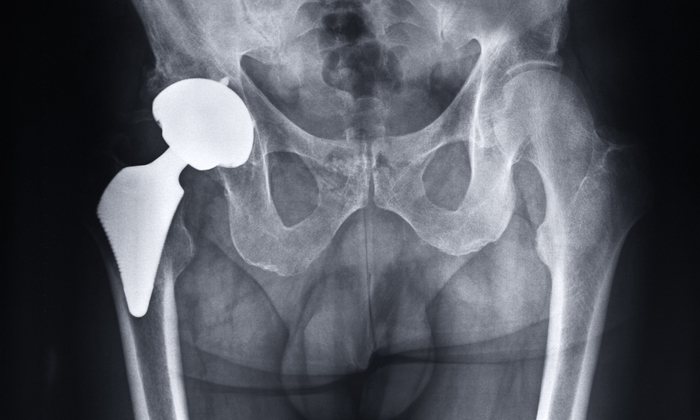

The role of genetic factors in pain after hip replacement

Patients with a form of IL6 gene were more likely to need higher doses of pain medication

hip replacement